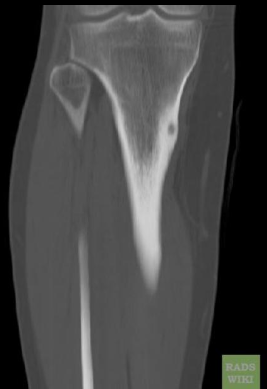

Cisto ósseo aneurismático

Acomete paciente jovem (fise aberta);

Localização excêntrica, aspecto em favo de mel no RX;

Pode ter reforço periosteal;

RM:lesão multicística; Septos + nível liquido-liquido (lesões dx diferencial: COS fraturado, COA, TCG ou osteossarcoma telangiectásico).

Primário ou Secundário à outros tumores: TCG, DF, Condroblastoma.